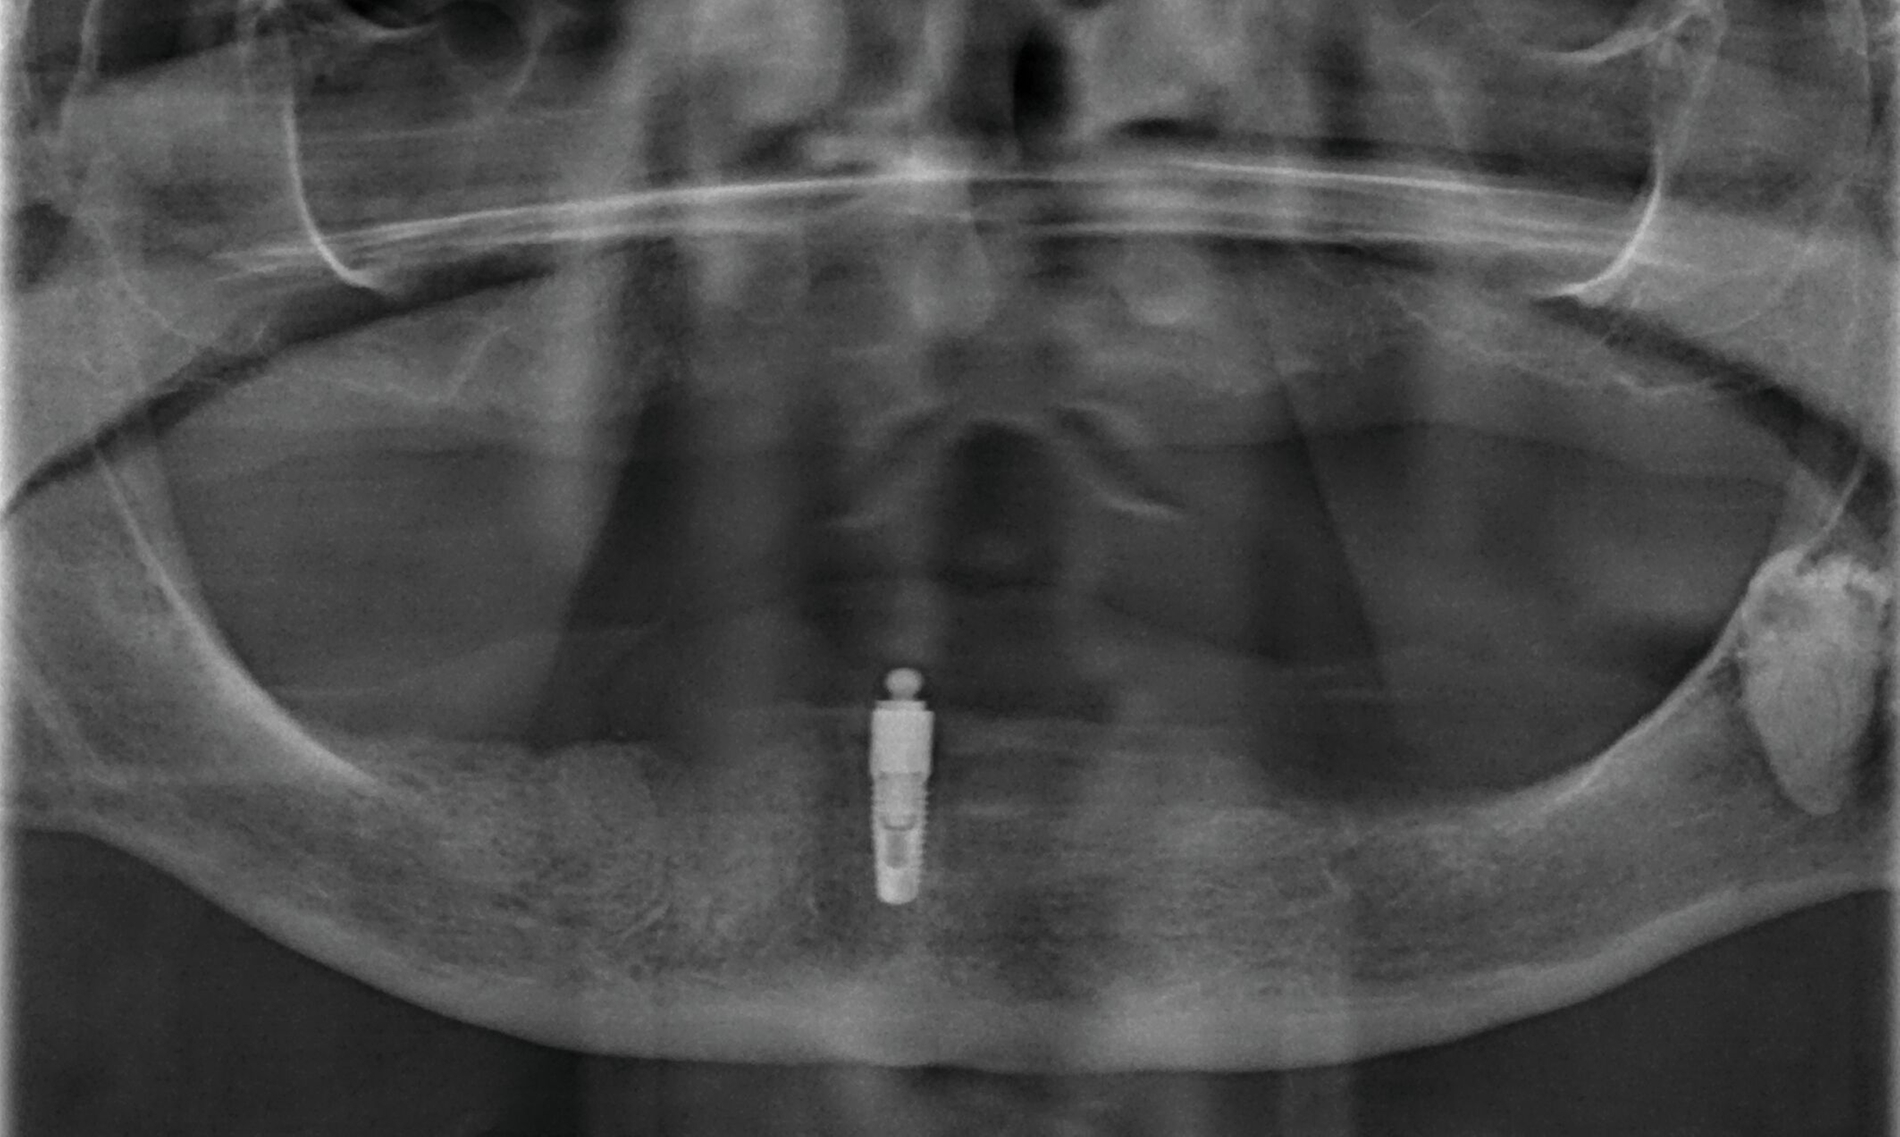

In einer von Kiel initiierten, DFG-geförderten, multizentrischen Studie mit 158 Ein-Implantat-Prothesen war die Implantat-Verlustrate nach fünf Jahren bei Sofortbelastung des Implantats höher als bei Spätbelastung (15,3 Prozent versus 3,8 Prozent) [Kern et al., 2018]. Die neun Implantatverluste in der Sofortbelastungsgruppe traten in den ersten drei Monaten nach Insertion auf. In der Spätbelastungsgruppe musste ein Implantat bei der Freilegung und ein weiteres nach fünf Jahren entfernt werden (Abbildung 3). Die postoperativen Beschwerden waren bei Sofortbelastung höher als nach Spätbelastung [Mundt et al., 2017]. Nach der Prothesenstabilisierung war eine deutliche Verbesserung der Kaueffizienz ohne Unterschiede zwischen den Belastungsprotokollen zu beobachten, die den gesamten Fünf-Jahres-Beobachtungszeitraum anhielt [Passia et al., 2022]. Die Patientenzufriedenheit [Passia et al., 2017] und die mundgesundheitsbezogene Lebensqualität [Schwindling et al., 2018] wurden ebenfalls spürbar verbessert.

Der Nachsorgeaufwand scheint jedoch nicht unerheblich zu sein. Von den über fünf Jahre nachverfolgten 102 Prothesen mussten 37 wegen Prothesenbasisfrakturen repariert werden, darunter elf mehrmals. Weiterhin wurde 123 Matrizeninserts und 14 Kugelköpfe im Studienverlauf ausgetauscht. Mögliche Komplikationen bei Ein-Implantat-Prothesen werden in einer Literaturübersicht mit einer berechneten jährliche Frakturrate von 10,8 pro 100 Kugelanker-Prothesen und 16,8 Nachsorgemaßnahmen pro 100 Locator-Prothesen bestätigt [Padmanabhan et al., 2020]. Die nachträgliche Einarbeitung einer Metallbasis verhindert Basisfrakturen [Pinheiro et al., 2021]. Insgesamt scheint die Ein-Implantat-Prothese im Unterkiefer eine einfache, minimalinvasive und kostengünstige Alternative mit hohen Implantatüberlebensraten bei Spätbelastung für ältere Patienten zu sein, die einem Vergleich mit Zwei-Implantat-Prothesen standhält. Bei der Wahl dieser Therapievariante für den Unterkiefer bei kompletter Zahnlosigkeit sollte der Nachsorgeaufwand berücksichtigt werden. Eine Sofortbelastung des mittig stehenden Implantats bleibt Ausnahmefällen vorbehalten.